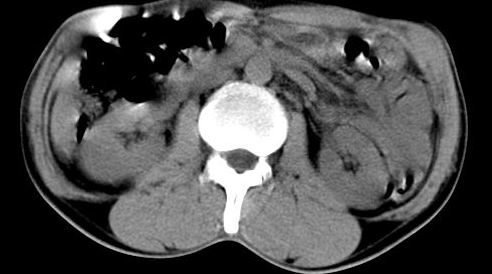

病人资料:男,50岁,上腹部隐痛,消瘦乏力,有乙肝病史二十余年,b超提示肝内内占位。

由于是基层医院,机器速度跟不上,增强效果差,请各位老师也看看!

肝右叶后下内侧段占位:肝癌可能性大。胰腺占位可能,病人没有空腹准备。

肝右叶后段占位,肝癌可能性大。下腔静脉无移位。肾上腺占位不支持?